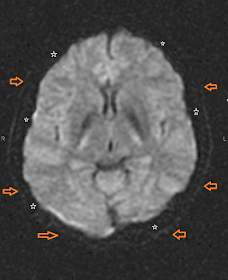

A continuación se muestran algunas imágenes de TRM craneoencefálica, potenciadas en Difusión Isotrópica y se destacan sus características diferenciales con las demás. Los más característico es el aspecto algodonoso, difuminado, que presentan las partes blandas encefálicas que, en condiciones normales, se representan en una tonalidad gris; los huesos del cráneo y del macizo facial, aparecen oscuros con algunos artefactos de susceptibilidad magnética en la base craneal. Y el líquido cefalorraquídeo y el gas de los senos paranasales también se reproducen en oscuro.

FIGURA 3) En ésta, se identifica el parénquima encefálico, contorneado por un fino trazo que corresponde a la piel (flechas). Los peñascos tambien se representan como dos sombras oscuras (asteriscos)

FIGURA 4) El trazo de la piel se observa con mayor nitidez (Flechas)

FIGURA 5) Entre la piel (flechas) y el parénquima encefálico se observa una banda oscura que representa al cráneo y a la grasa subcutánea.

FIGURA 6) La banda oscura que representa al hueso craneal se hace más patente en esta imagen (asteriscos) delimitada siempre por la linea del cuero cabelludo (flechas).